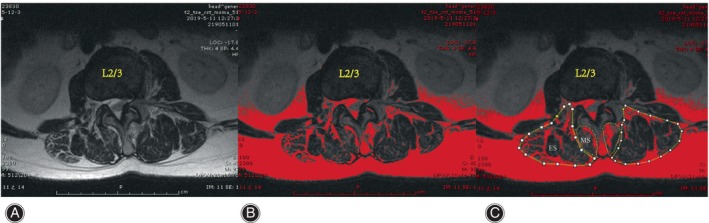

The cross‐sectional areas (CSAs) of the MS and ES muscles at the apex of the primary and fractional curves were determined by tracing the muscle’s fascial boundary using Image J‐win64 software.ref. os14185-bib-0025 To evaluate fat infiltration, the fat infiltration area (FIA) within the total CSA of both muscles was quantified using a threshold technique.ref. os14185-bib-0026 Subsequently, the percentage of fat infiltration area (%FIA) relative to the total CSA was calculated (Fig. 2). The central image, corresponding to the apical vertebra, was selected for PM assessment (Fig. 3). The convex side encompassed both the primary curve’s convex side and the compensatory curve’s convex side, with the difference value between the concave and convex sides indicating the degree of asymmetric PM change. We defined the difference of more than 3% between concave and convex paravertebral muscle fat infiltration as asymmetrical threshold. Paravertebral muscle parameters and imaging parameters were measured respectively by two observers independently, blinded to the patients’ characteristics.